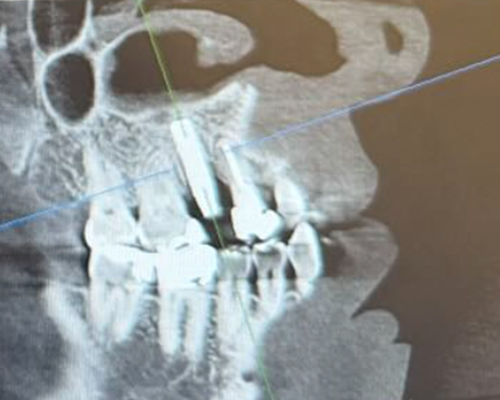

米国の技術×専属技工士×精密機器のフル活用で「短期治療」を実現!

米国の先端治療を安価で

年間1,000症例以上の 「世界レベル」オペ実施